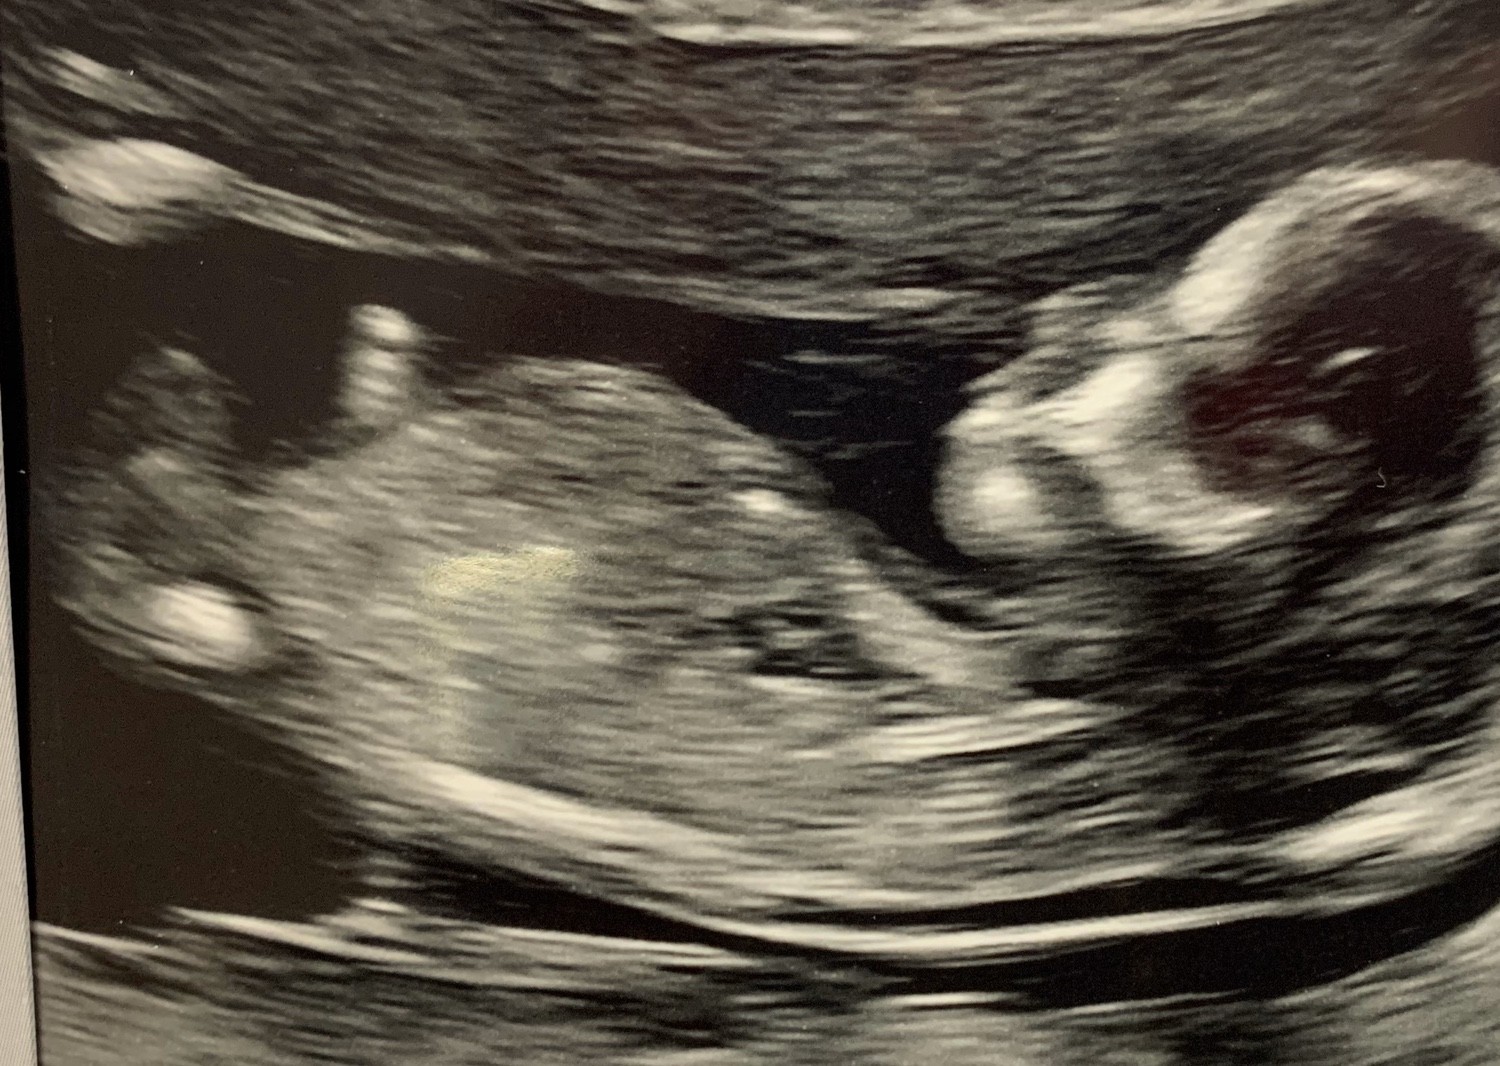

Płeć w 18 tygodniu.

Cześć :) czy płeć można już określić w 18tc?

Czy te dwie kulki miedzy nogami mogą wskazywac na chłopca? Dolaczam zdj.

• 81676932_2712087178882737_2870614496919945216_n.jpg

81676932_2712087178882737_2870614496919945216_n.jpg

57,4 KB · Wyświetleń: 954